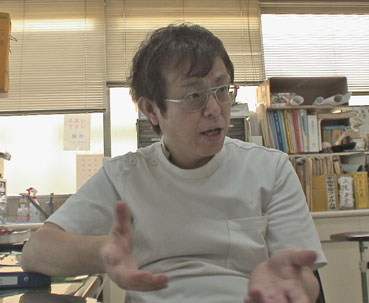

2006年11月10日、バンジャの足骨折治療の状況を、アエバ外科の尾川先生に聞いた。

尾川先生から説明があった。 |

| レントゲンで見る限り順調だ。 |